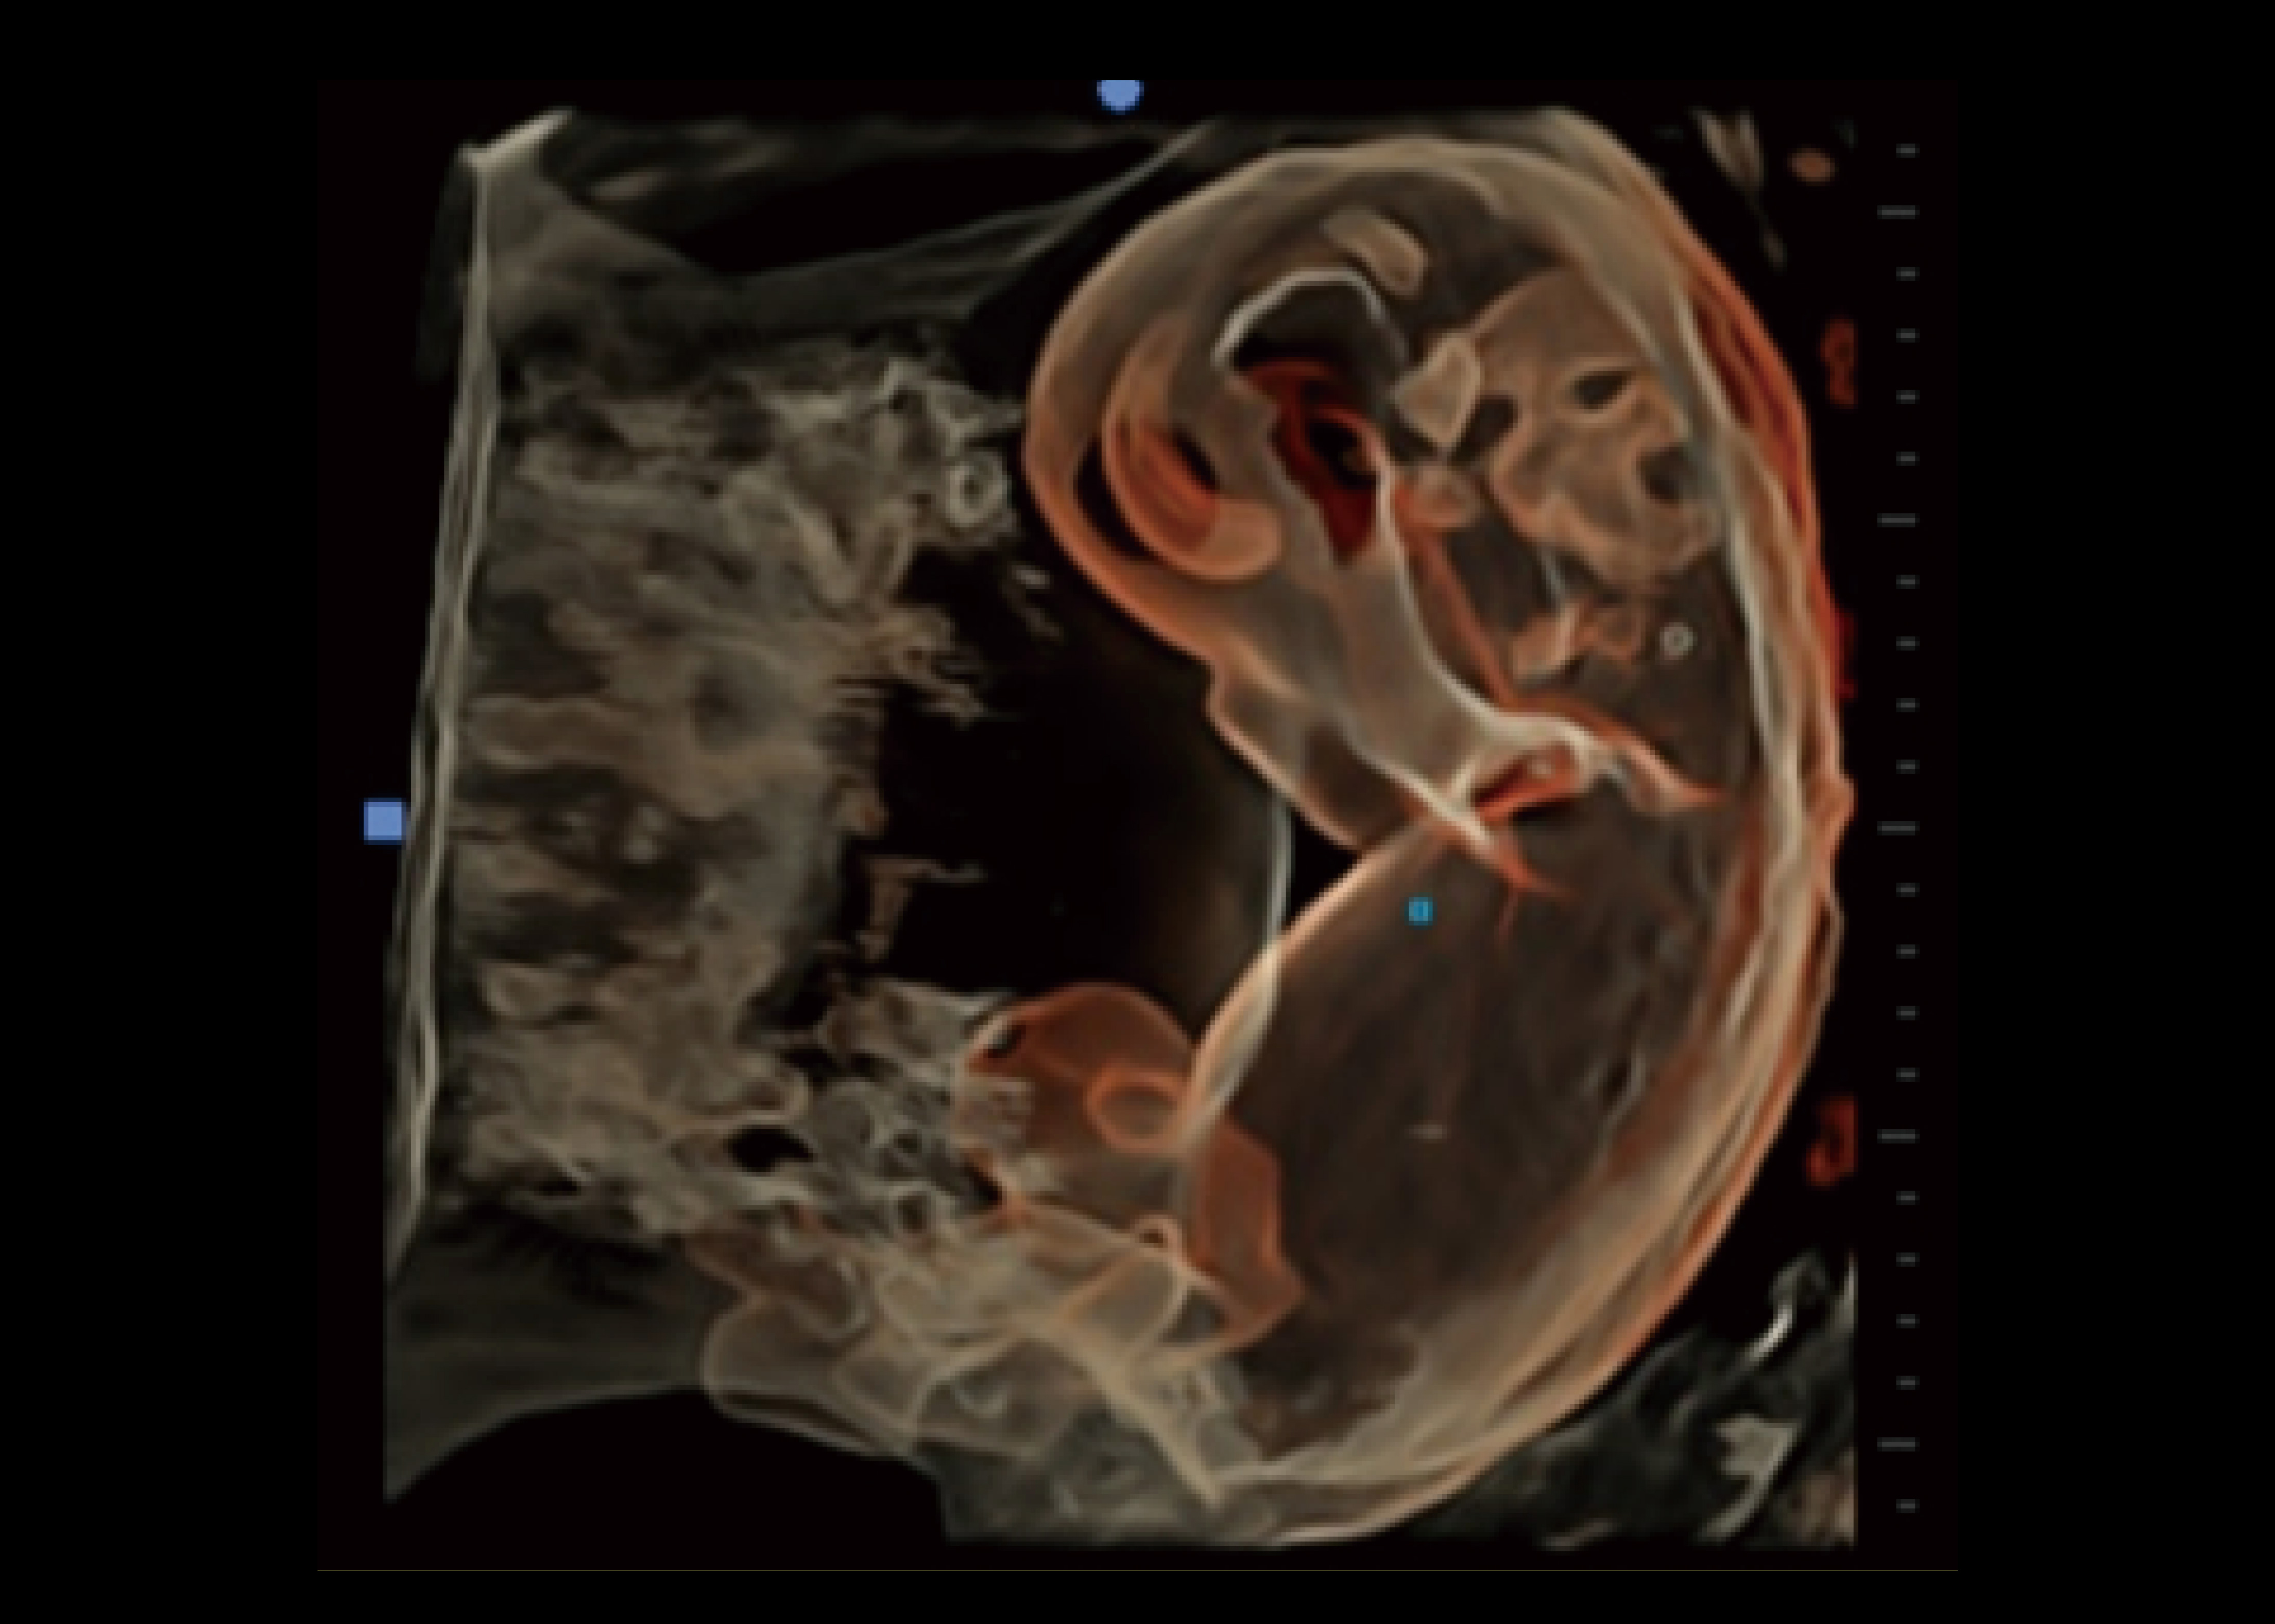

Anwendungen

Der CHISON Premium-Trolly-Farbdoppler XBit 90 wurde entwickelt, um Ärzten eine zeitgemäße und hochmoderne Erfahrung in der klinischen Diagnose zu bieten, indem er verbesserte Ansichten, moderne künstliche Intelligenz und einen reibungslosen Arbeitsablauf bietet.

Ausgestattet mit modernster Technologie ist das wagenbasierte Ultraschallgerät XBit 90 von CHISON, die beste Wahl für die Anwendung der allgemeinen Bildgebung.

· Geburtshilfe/Gynäkologie · Urologie - Kardiovaskulär - Innere Medizin · Intensiv -Critical Care -Radiologie · Notfallmedizin · Anästhesie · Pädiatrie

Erstaunliche Bildqualität

Wir freuen uns, Ihnen mitteilen zu können, dass wir jetzt mit diesem neuen Ultraschall XBit 90 arbeiten. Seine Anwendungen in den verschiedenen medizinischen Fachgebieten sind wirklich erstaunlich, nicht nur für die Qualität der Bilder, sondern im Wesentlichen für den Beitrag zur Klarheit der Diagnose von verschiedene Pathologien und ihre adäquate Behandlung. "

SonoCrystal

● Bereitstellung von Kontext- und Oberflächeninformationen.

● Ermöglicht ein genaues Verständnis der Anatomie des Patienten.

● Unterscheidet mühelos zwischen Weichgewebe und Struktur.